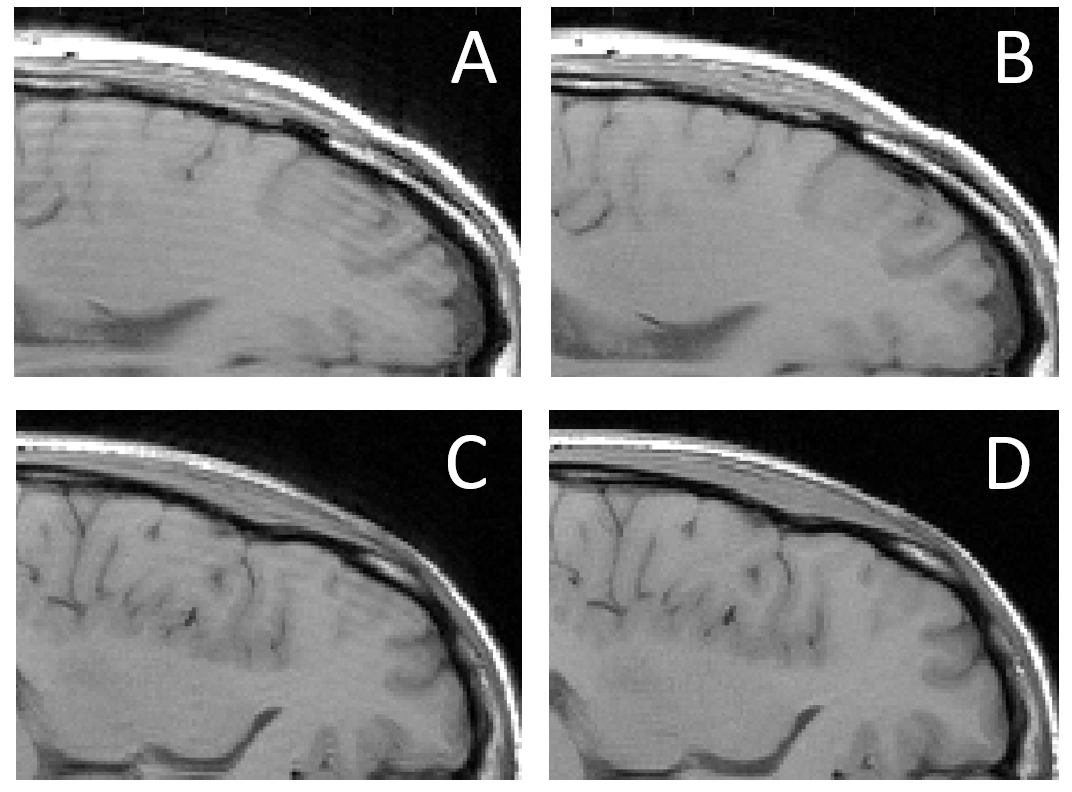

Two representative examples of in-vivo motion-corrupted ChoCo slices and their restored versions based on DNN predictions are presented in Figure 9. These qualitative results show that DNN estimations were accurate enough to allow the removal of most of the motion artifacts.

Refer to caption

Figure 9: (A and C) Representative examples of classical T1w Spin-Echo acquisitions corrupted in-vivo following the ChoCo procedure for generating controlled motion artifacts. (B and D) Restored images by phase cancellation and iterative NUFFT reconstruction from DNN motion parameter estimations. (The two rows show the same anatomical region for two different subjects.)